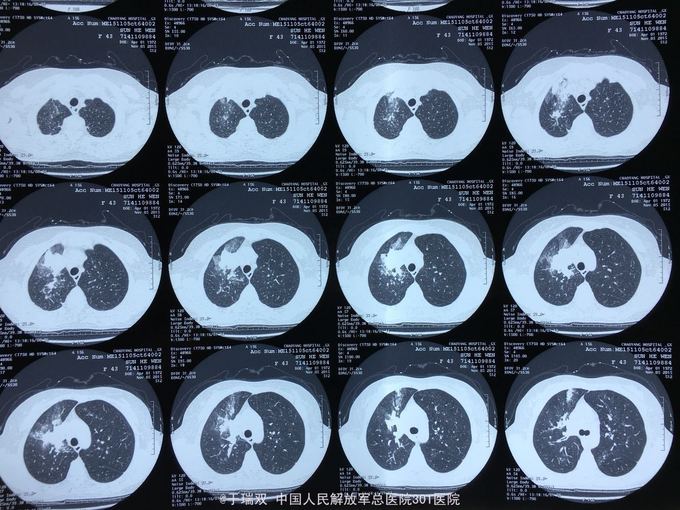

患者中年女女性,2014年10月无明显诱因出现咳嗽咳黄白痰,伴有喘息,自行药物治疗无好转。2014年11月下旬就诊于北京某医院诊断为“变应性支气管肺曲霉病、真菌性肺炎”先后给予伊曲康唑静滴及口服伏立康唑抗真菌、平喘等治疗后症状好转。复查CT炎症也吸收好转,于2015年3月停用以上药物。2015年11月患者再次出现上述症状,胸部CT见右肺班片状实变影,就诊于我院给予左氧氟沙星、西替利秦及化痰止咳治疗后略有好转,遂住院。2015年11月5日CT(图1、2),2015年12月14CT(图3、4、5、6)